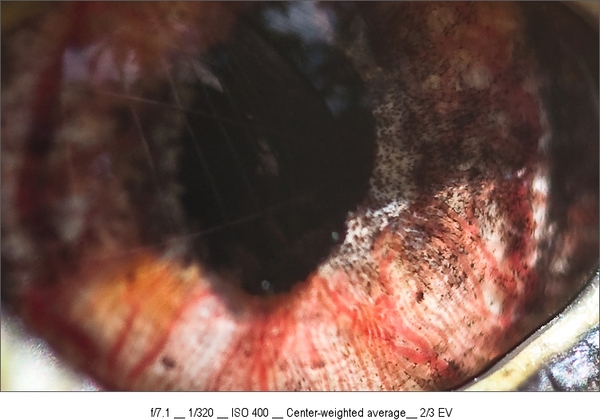

Fotograaf: Dushi

DSC_5887-11

Gemaakt op: 22-01-2010 18:21:54